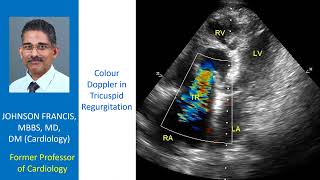

Colour Doppler in Tricuspid Regurgitation video

Color Doppler for Tricuspid Regurgitation

Color Doppler for Tricuspid Regurgitation Colour Doppler in Tricuspid Regurgitation

Colour Doppler in Tricuspid Regurgitation Tricuspid Regurgitation - Colour Doppler Echocardiogram